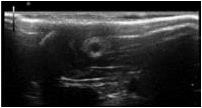

Ultrasound image of the morphology of a chitosan nerve conduit in a rat model of sciatic nerve defects at three weeks after modeling.

August 25, 2014 — New simple and effective methods are needed to better evaluate the outcomes of repair using nerve conduits in vivo. Ultrasound is a common noninvasive clinical detection modality that has been used in many fields. However, ultrasound has only rarely been used to observe implanted nerve conduits in vivo. Hongkui Wang and co-workers from Affiliated Hospital of Nantong University report the first use of ultrasound to noninvasively observe the changes in chitosan nerve conduits implanted in rats over time. The ultrasound imaging clearly showed whether there are unsatisfactory complications after implantation, such as fracture, collapse, bleeding or unusual swelling of the nerve conduits; and reflected the degradation mode of the nerve conduit in vivo over time. Ultrasound, as a noninvasive imaging modality, can be used as a supplementary observation method during conventional animal experiments on peripheral nerve tissue engineering. The relevant study has been published in the Neural Regeneration Research (Vol. 9, No. 14, 2014).